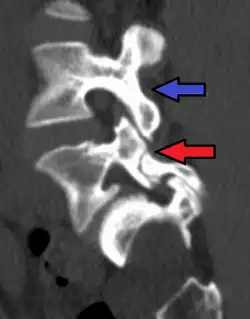

Computed tomography

Commonly known as a CT Scan or CAT scan, this form of imaging uses x-rays to produce multiple cross-sectional images, or "slices", through a part of the body. This allows a physician to evaluate the body in greater detail than an x-ray allows. For this reason the CT scan is much more accurate in detecting spondylolysis than an x-ray. Bone scintigraphy combined with CT scan is considered the reference standard, which means that it is best at detecting spondylolysis.[16][18]